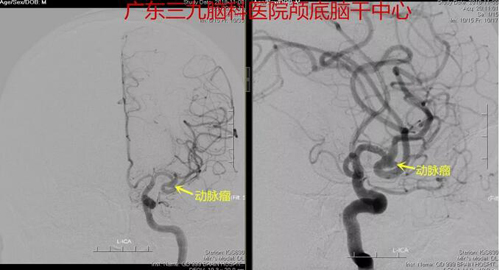

周某的情况正是颅内动脉瘤出血,进一步的检查结果显示,左侧大脑中动脉瘤M1段分叉部动脉瘤,大小约2mm*4mm。与家属充分沟通后,由张良主任主刀,成功夹闭动脉瘤。

图2:术前DSA造影示左侧大脑中动脉瘤M1段分叉部动脉瘤,大小约2mm*4mm颈宽,朝后外侧生长,瘤顶可见小